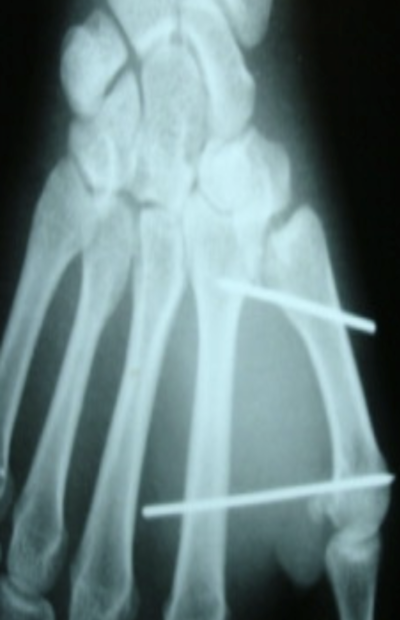

Brochage selon Iselin

L’intervention se déroule au bloc opératoire, sous anesthésie loco-régionale (seul le bras est endormi), en ambulatoire (vous entrez et sortez de l’hôpital le même jour que votre intervention). Les cicatrices réalisées sur le dos de la main mesurent quelques centimètres et dépendent de la nature de la fracture et du matériel nécessaire à la réduction de cette dernière.

L’intervention la plus classique est le brochage selon Iselin (mise en place de 2 broches).